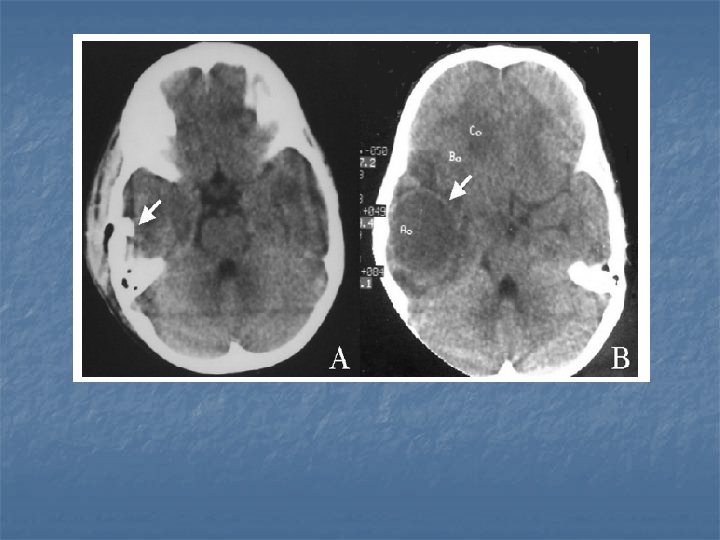

MSS Tbc. Komplikasyonları n n n Hidrosefali : Pediatrik olguların % 8090’ında gelişir. Kranyal sinir felçleri İnfarkt: % 20 -50. MCA veya ACA veya perforanların beslediği alanlarda görülür. Bazal ganglionlardaki ve talamustaki infarktlar tipiktir